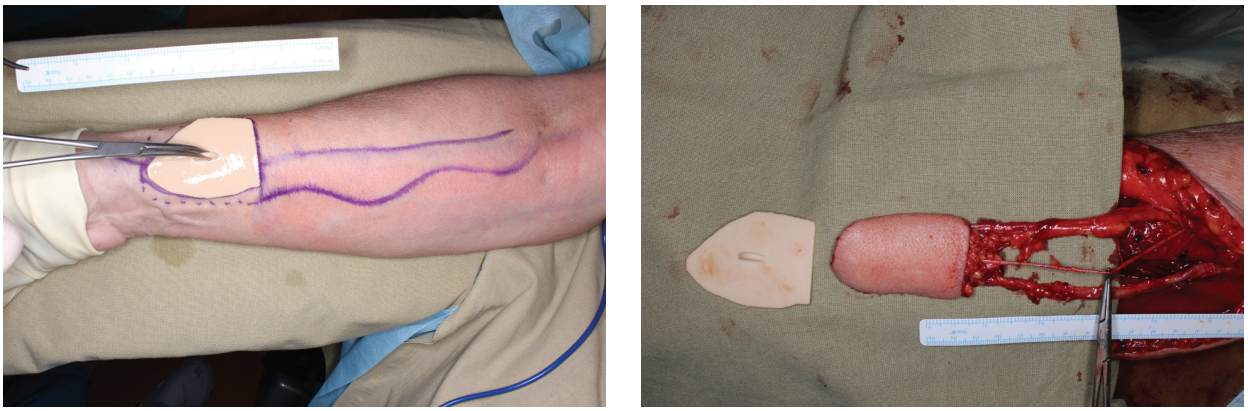

Further on the basis of mathematical interpolation methods using Slicer and Blender software the selected volume of the formation was determined taking into account the indentation from the tumor borders of 1.5 cm to reach the edges of the resection borders R0. The obtained data were converted to surface area and adapted to the topography of the donor arm by placing the surface of the stencil template over the axial vessels (radial vessels) to incorporate them into the flap. The surface area of the flap was increased by 15% taking into account possible flap shrinkage after radiation therapy. Thus, two templates were made: a resection template for hemiglossectomy and a template for cutting the skin area of the radial flap (Fig. 1).

Surgical interventions were performed by two teams of surgeons according to the standard protocol. The first team of surgeons performed tongue tumor ablation using a resection template, cervical lymphodissection, and isolation of recipient vessels of the neck (Fig. 2).

The second team of surgeons simultaneously isolated the radial flap using a template. The average time of the resection stage was 87 min. The average time of flap harvesting was about 115 min. Radial flap isolation in all cases was performed with inclusion of the radial artery and vena comitans, as well as the lateral cutaneous nerve of the forearm (Fig. 4). Following flap isolation, the vascular pedicle of the graft was cut off and the graft was moved into the oral cavity.

Fig. 4. Marking a flap using a template. Radial flap on a vascular pedicle